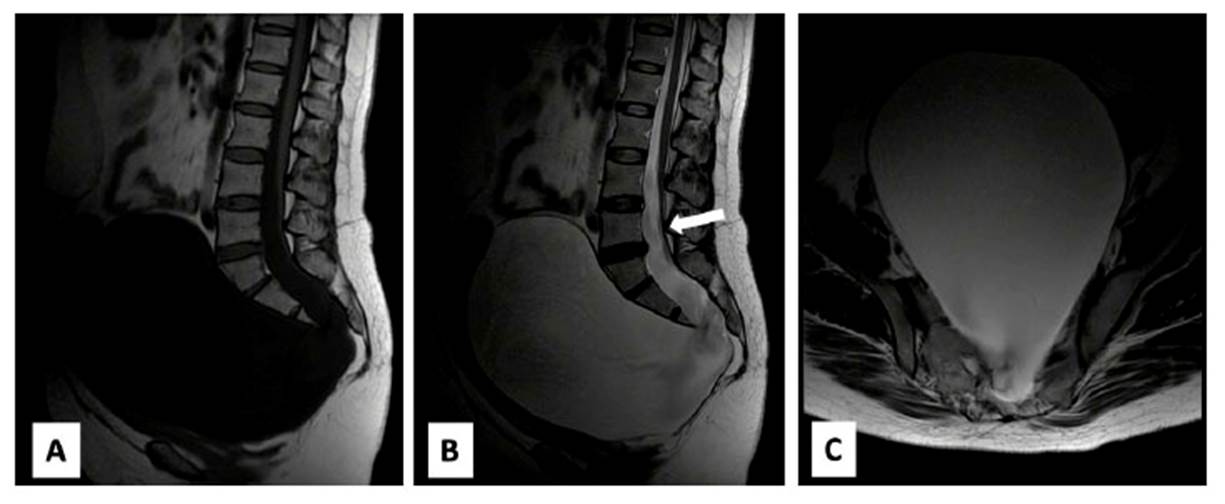

Paciente mujer de 42 años de edad, nuligesta y con antecedentes de quiste de ovario desde los 25 años, infección urinaria recurrente y síndrome ansiodepresivo. Se presenta en nuestro hospital con el síntoma principal de distensión abdominal e incomodidad en miembros inferiores sin un territorio radicular definido, cursa con estreñimiento crónico de 15 años de evolución y cefalea a las maniobras de Valsalva. El examen físico no mostró alteración neurológica, pero sí hemiabdomen inferior con gran distensión y cierta resistencia a la palpación. Los exámenes de imágenes mostraron evidencia de MSA, disgenesia sacra, masa quística ovárica izquierda, médula anclada, malformación de Chiari y doble uréter izquierdo (Figura 1 y Figura 2), sin alteraciones anatómicas digestivas y con la función renal normal, por lo que se diagnóstica MSA gigante tipo I de Cheng y síndrome de Currarino incompleto.

Figura 1 Resonancia magnética (RM) lumbosacra. 1A imagen sagital T1: proceso expansivo hipointenso en cavidad pélvica. 1B Imagen sagital T2: quiste que depende de saco dural a través de un defecto a nivel de S3 de 172 x 152 x 129 mm, también se muestra médula anclada (flecha). 1C Imagen axial T2 a nivel de S3

El tratamiento que se aplicó fue una laminectomía S1/S2/S3 y luego, con microscopio y monitoreo neurofisiológico de las raíces lumbares bajas y sacras, se seccionó el filum terminale. Después de comprobar que no había raíces dentro del saco herniario con el ostium a la altura de S3, el líquido cefalorraquídeo (LCR) se aspiró de la cavidad. Para terminar, el extremo proximal se liga al saco dural y el defecto óseo queda sellado con fascia muscular, injerto de duramadre y pegamento de tejido (Figura 3).